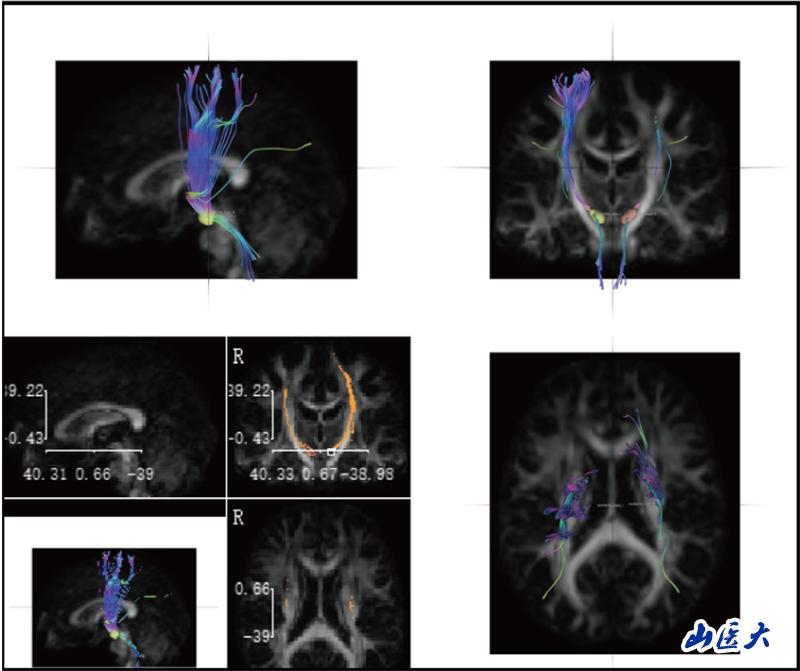

神經解剖學教學長期面臨"結構隱匿性"與"空間復雜性"的雙重挑戰。傳統的大體標本和平面模型難以展現纖維束、核團等微觀結構的空間關系,易導致學生神經解剖結構認知困難。研究團隊針對這一痛點,創造性引入前沿神經影像技術—DSI Studio纖維束成像系統。該技術通過對擴散磁共振成像(dMRI)數據分析,實現纖維路徑智能追蹤、三維動態重建及多維度交互可視化,構建起"影像解剖-病理對照-臨床關聯"的一體化數字教學體系。

研究團隊創新性構建"理論-操作-臨床"三階整合教學模式,基于DSI Studio纖維束成像技術開展教學實踐。選取38名低年級醫學生為對象,通過整合人類連接組計劃(HCP)標準腦數據庫、帕金森病進展標志物計劃(PPMI)及臨床腦出血病例影像數據,建立"正常-病理"雙模態教學資源庫。此教學實踐改革,不僅提升了學生神經解剖結構的空間理解力,并培養了學生從解剖結構認知到功能損傷解析的臨床思維能力。

陸利教授團隊長期致力于神經退行性疾病研究,此次將神經前沿進展轉化為教學資源,實現了"科研數據教學化、教學過程科研化"的良性循環,使學生掌握解剖基礎知識的同時,還可以智能化觀察病理狀態下的神經結構,為培養早期臨床思維提供創新路徑。